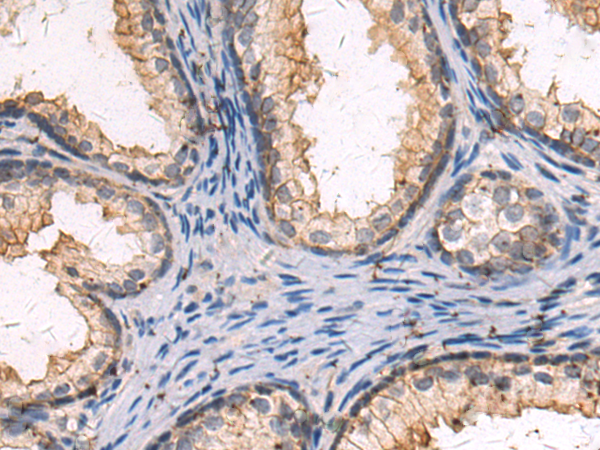

分类: 科研抗体货号: P10583别名: FXY2; RNF60; TRIM1; MRX101应用: IHC反应种属: Human, Mouse